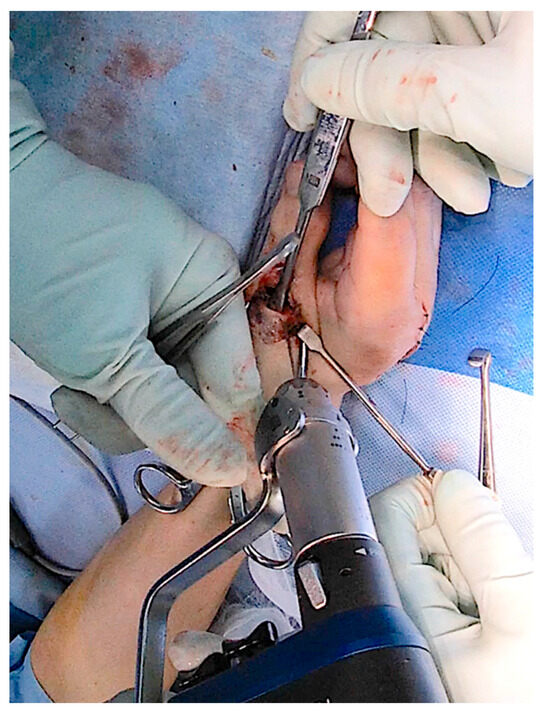

Trends in Rheumatoid Hand Surgery: Indications, Techniques, and Outcomes

by Masanori Nakayama, Yasuhiro Kiyota, Soichiro Nakamura and Mitsuru Yagi

J. Clin. Med. 2025, 14(2), 319; https://doi.org/10.3390/jcm14020319 - 7 Jan 2025

Rheumatoid arthritis (RA) causes persistent synovitis and arthritis, resulting in joint deformity and destruction throughout the body. As RA medications have evolved over the past 30 years, the surgical indications and techniques for RA joint deformities have changed. The aim of this review [...] Read more.

Rheumatoid arthritis (RA) causes persistent synovitis and arthritis, resulting in joint deformity and destruction throughout the body. As RA medications have evolved over the past 30 years, the surgical indications and techniques for RA joint deformities have changed. The aim of this review article is to summarize the recent trend of surgery for rheumatoid hand/finger deformities in previous reports and to present our recent surgical methods and outcomes for these deformities. A typical hand and finger deformity caused by RA is ulnar deviation, which is mainly caused by joint laxity and dislocation of the metacarpophalangeal joints, in addition to extensor tendon dislocation and/or wrist joint deformity. Although the incidence of hand/finger deformity and ulnar deviation caused by RA is decreasing due to advances in RA medications, patients with long-term RA or those with difficult-to-treat RA may still develop hand/finger deformity and ulnar deviation. If the hand/finger deformity is mild, it can be reduced manually, and conservative treatment with orthoses or splints may be required. If joint pain is severe despite good medical control of RA, or if the patient hopes to improve the appearance of the hand or fingers, surgical intervention is required. If there is only subluxation of the joints, which preserves their structure, reconstruction with only soft tissue surgery may be required. For example, for swan-neck deformity and boutonniére deformity, two of the most typical finger deformities due to RA, when the joint structures are almost intact and can be corrected manually, we opt for a surgical procedure that involves only soft tissue manipulation without the use of prosthetic implants. For ulnar deviation without joint destruction, we usually use a soft tissue-only surgical procedure. Our results have shown that the soft tissue-only surgery for ulnar deviation is as effective as joint replacement with implants. If the destruction of the joint has occurred and its dislocation/subluxation cannot be reduced manually, implant arthroplasty becomes necessary. If the joint destruction is severe, only intra-articular arthrodesis is required. In the era when RA can be controlled by medication, the hand surgeon should not overlook the change in the stage of the rheumatoid hand and should perform surgical intervention via the appropriate surgical method. Full article

Show Figures

Figure 1